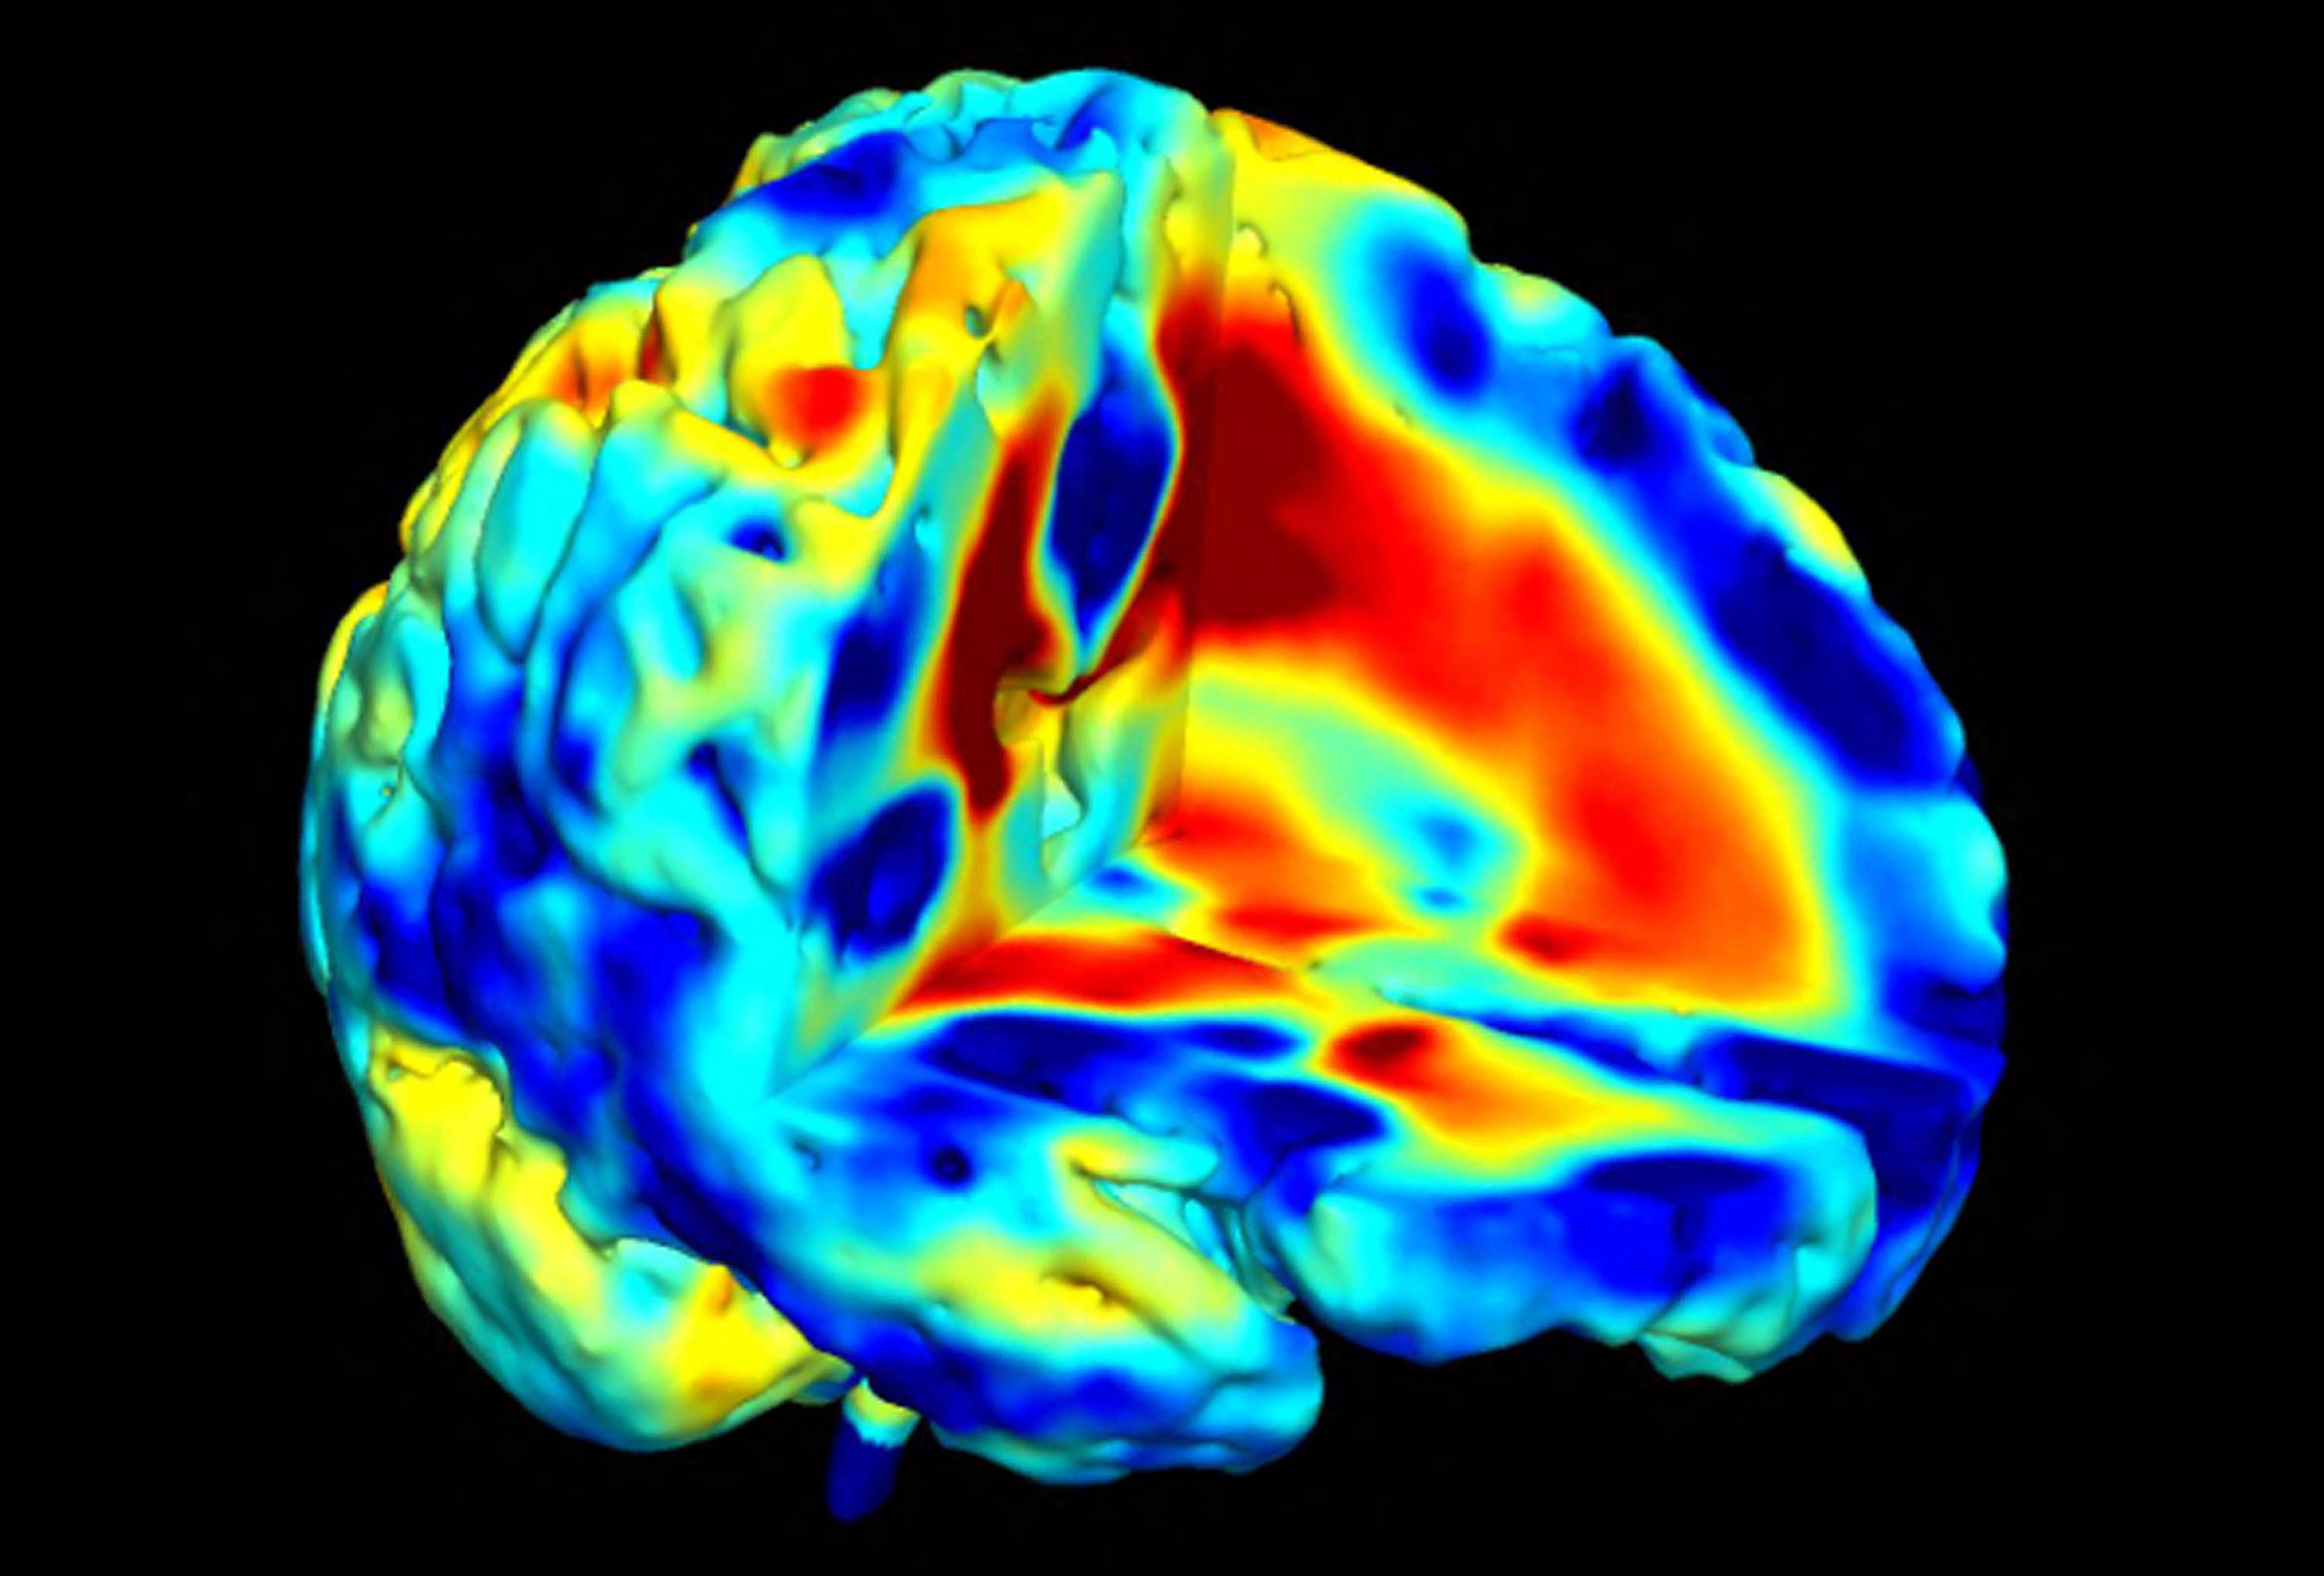

Traditionally, neuromodulation targets the same spot brain region in all patients’ brains. The Geneva team is moving away from this one-size-fits-all model.

“Brains come in all shapes and sizes. If we target the same coordinates in everyone, we will get varying results or no result in some patients,” Bègue explains.

Instead, researchers map circuits at the individual level. “We conduct MRIs on each patient to map their own brain circuit, which serves as brain stimulation targetdetermine their ideal target,” she says. “The stimulation parameters are then adapted accordingly.”